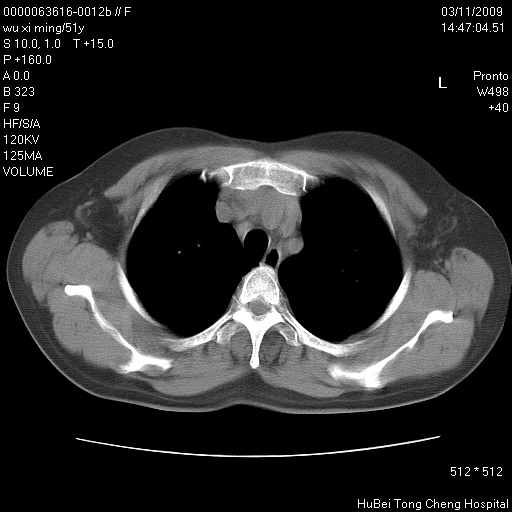

患者 女,51岁。因“胆囊炎,胆囊结石”,行常规术前胸部x线检查发现:右上肺结节病灶,建议行进一步检查。患者无咳嗽、咳痰及咯血等呼吸道症状,近期出现背部疼痛不适。

胸部ct轴位平扫(层厚10mm,螺距1.5,重建间隔10mm;部分层面:层厚3mm,螺距1.0,重建间隔3mm),图像如下:

右肺周围型肺癌伴肺内转移信胸椎转移

集束征,胸膜牽拉征,毛刺,淺分葉高度提示ca.

右肺周围型肺癌伴肺内转移及胸椎转移。已无手术机会。